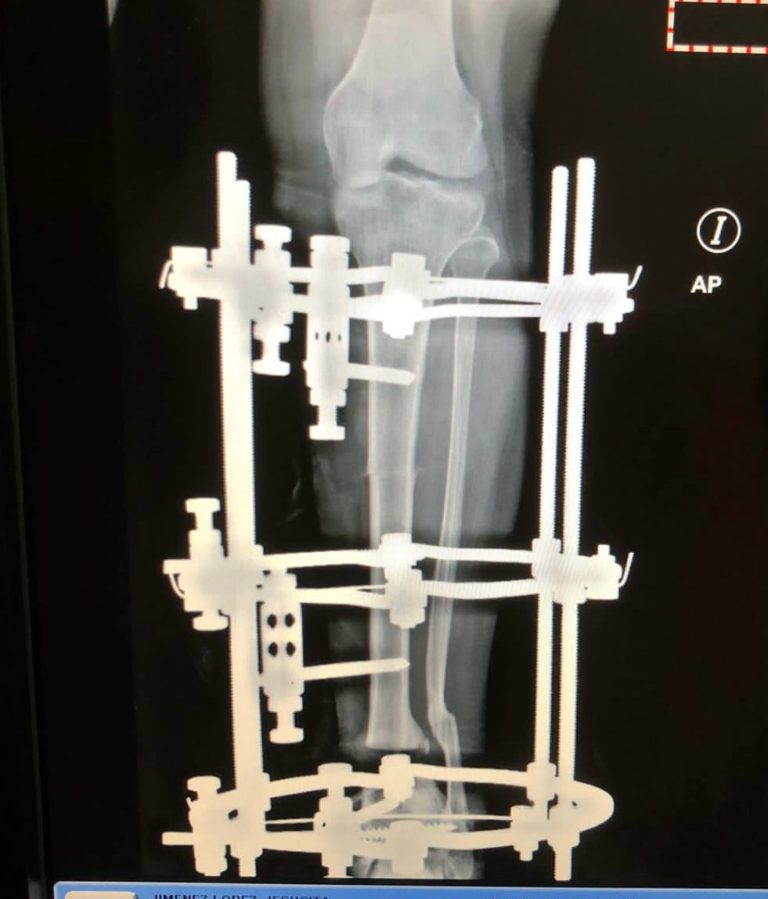

El doctor Julio Landrón, director general del centro hospitalario, dijo que los pacientes intervenidos presentaban lesiones graves, por lo que se le fueron colocadas fijaciones externas de última generación.

“Con la finalidad de alargar los miembros inferiores, que quedaron con importante acortamiento, debido a fractura de alta energía, estos son pacientes de cirugía reconstructiva a los cuales se realiza entre dos y tres procedimientos quirúrgicos para llevar estos pacientes a la normalidad, pacientes que anteriormente cuando no existía una Unidad de Reconstrucción Ósea, como la tiene el Ney Arias Lora en estos momentos , eran llevados y le realizaron amputaciones en otros centros” dijo Landrón.

El especialista agregó que gracias a la alta tecnología y el personal humano capacitado, les permitió poder preservar los miembros superiores e inferiores a los pacientes que tienen lesiones de cuidado con pérdida ósea importante, para que en el menor tiempo puedan integrarse a la vida productiva.